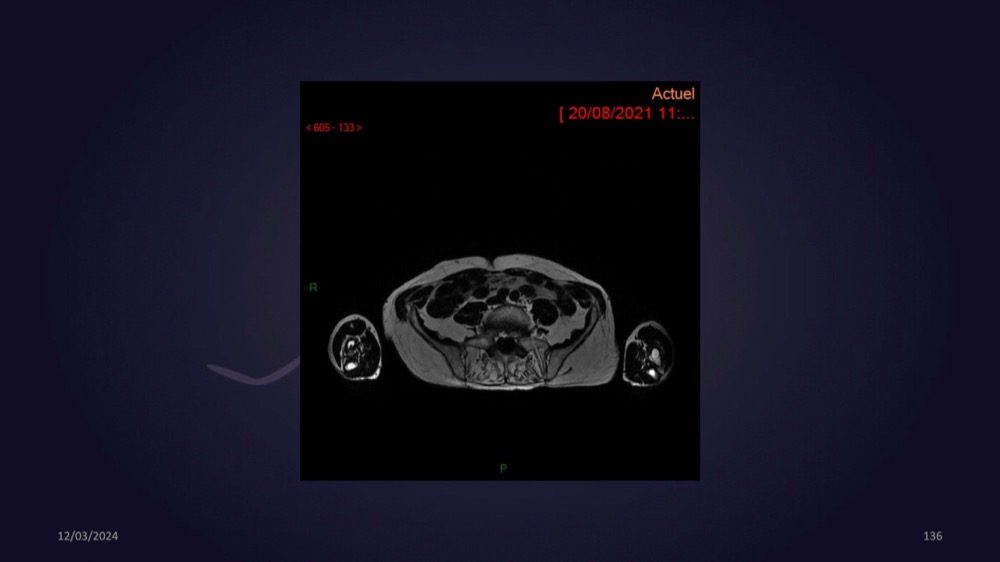

Mezhgani / Dimitri Boulos / Carlier 23/03/2022